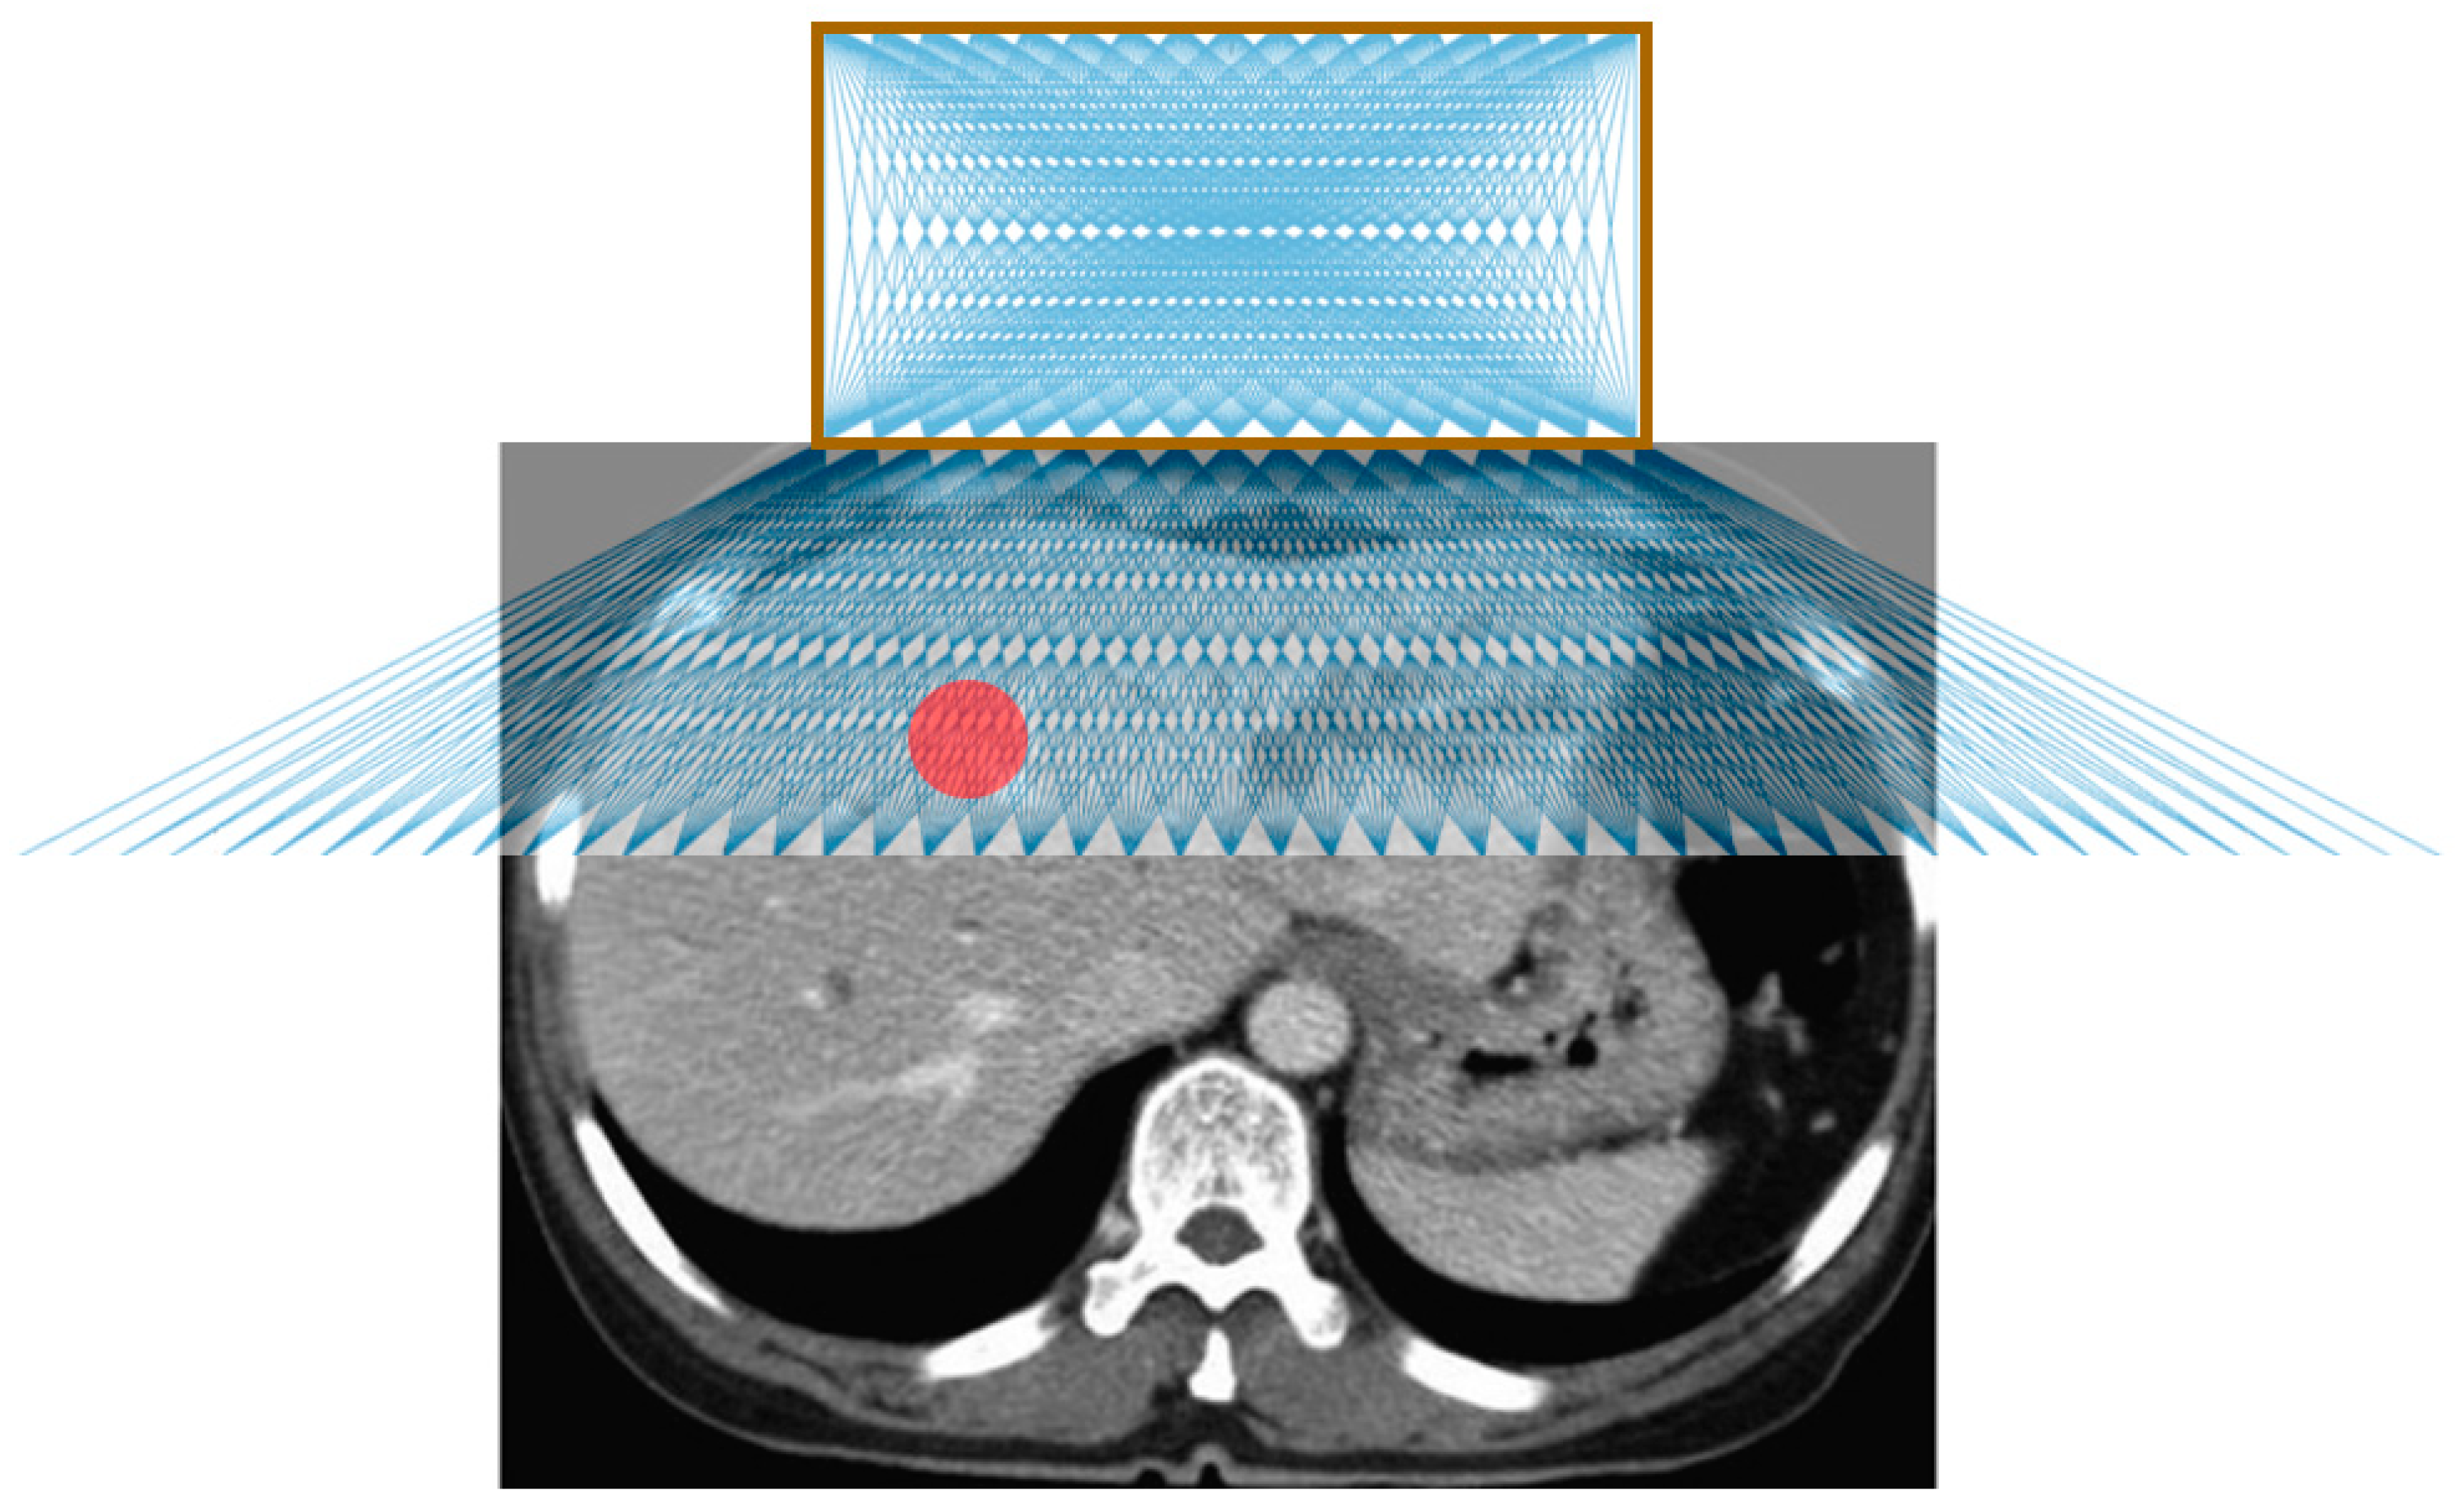

Figure 4 shows the possible needle trajectories in the transverse plane provided by the gridlines on the origami lesion-targeting device. The discrete potential insertion locations correspond to RCA gridlines. The RCA grids provide a high density of discrete guidelines, while the puncturable device material offers a continuous workspace for potential needle insertions.

Figure 4.

Illustration of possible needle trajectories in the transverse plane. The brown square represents the lesion-targeting device, the red circle represents the target lesion, and the blue lines represent the needle trajectories.